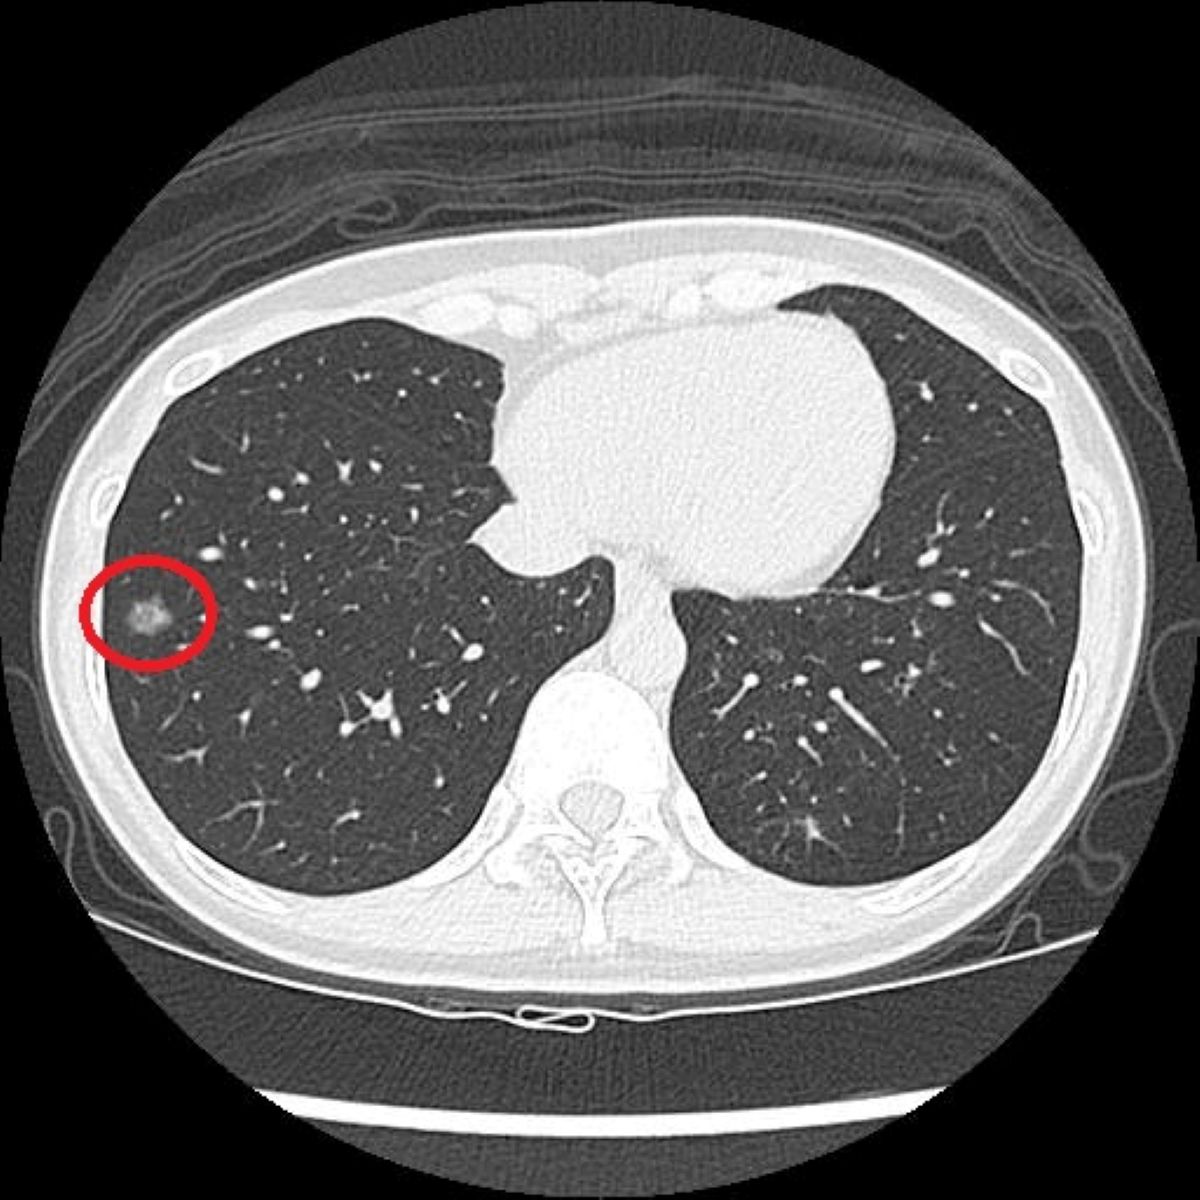

篩檢方面,過去是以胸部X光作為工具,但由於影像為2D平面,對於體積小或位置較隱蔽的病灶辨識能力有限;若是改以一般劑量的電腦斷層檢查,雖能提升解析度,但其輻射劑量相對較高,且需較長時間代謝,不適合作為常規或大規模篩檢工具。而LDCT篩檢則是利用比傳統電腦斷層更低的輻射劑量,從多個角度掃描胸腔,重建出清晰的橫切面和立體影像,有助於偵測肺部的微小結節。洪嘉聰醫師指出,相較於傳統胸部X光只有少數約7%的受檢者會出現疑似異常影像,LDCT能使初次篩檢的陽性比例提升至約23%~24%,大幅增加早期病灶被發現的機會。

過去有長期的吸菸史的41歲的陳小姐,在醫療團隊的協助下戒菸近兩年,雖然沒有任何不適,但仍定期留意自身健康。因符合政府公費「低劑量電腦斷層(LDCT)」篩檢條件,她依建議至台北慈濟醫院接受檢查,卻意外發現右肺有一顆約1.2公分的毛玻璃結節,被轉診至胸腔外科門診,由洪嘉聰醫師進行單孔胸腔鏡微創手術切除病灶,術後病理檢查確診為肺腺癌第一期,目前定期回診追蹤中。